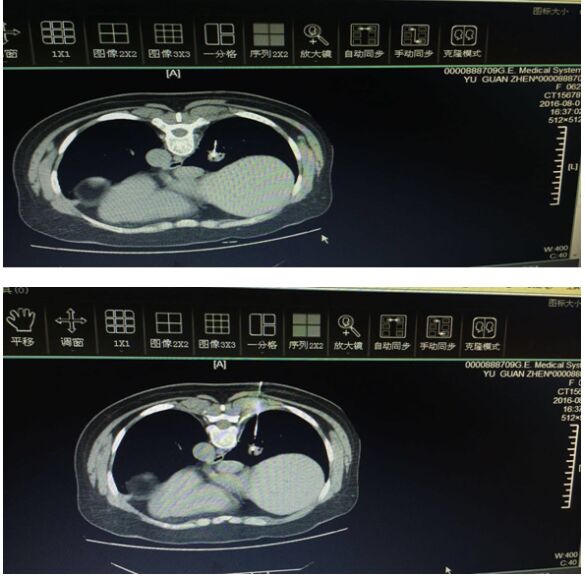

患者余某某,因“痰中带血”入住我院呼吸内科,增强CT显示:右肺下叶内基底段不规则软组织阴影,大小约2.5*2.5cm。在外院做过一次纤支镜、两次肺穿刺都未能明确诊断,故来我院诊治。结合患者年龄、反复咯血及胸部影像学特点,医生告知患者家属需排除肺部恶性疾病的可能,有行CT引导下经皮肺穿刺指征,但病灶小、位置深、距胸壁约9.3cm,且病灶位于呼吸动度大的下肺组织,穿刺难度极大,经过集体讨论、综合评估,与患者及其家属就操作风险及并发症等情况反复进行沟通,做好知情同意宣教、制定预案,拟于8月1日CT引导下经皮肺穿刺活检。

8月1日,患者于局部浸润麻醉、CT引导下经皮肺穿刺术,由今年6月才从德国进修介入术回来的李长毅副主任亲自操作。CT平扫确定穿刺进针位置及方向,并对患者进行呼吸训练,应用Temno可回扫穿刺针进行穿刺,总进针深度长达10余厘米,准确穿刺结节,并成功切割条状组织。完成穿刺标本采样后,CT再次回扫,仅发现少许针道出血,未见气胸发生。术毕安返病房,生命体征平稳,无心悸、胸闷、胸痛、咳血等不适。